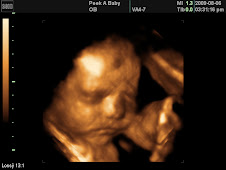

The Wilson Family witnessed God's beautiful miracle of life today when we saw our beautiful grandson Connor Wilson Womack weighing 8 pounds, 19 3/4 inches come into this world at 8:56 a.m. Our daughter Lauren went into pre-labor on the 17th at 3:30 am. She has been staying with us. We weren't sure if what she was experiencing was water breakage of bladder release. My mother and I decided to take her to the ER of Memorial Hermann at 12:30 pm. After the triage nurse checked her and discovered her water had ruptured, they admitted her. Lauren was so strong through the entire process. She had spent 9 months fearing so many things, the birth and being a mom. Like a true Wilson she stepped up to the plate and showed everyone what strength and heart are made of as she pushed this 8 pound baby into the world. It didn't end there, the motherly intent she wasn't sure she had, kicked in in full force for her little man Connor. He will not face this world alone, with Lauren as his mother he will always be safe and secure. As I did today when I stood hand in hand with my daughter during her delivery. I was so honored to be there with her, she showed even me what strength is about. Today, I witnessed not only the miracle of life but God's amazing grace has filled my heart on so many levels. Over the last year, I have learned so much about myself, God, my children and forgiveness. I know I have a long road to be where I should be in this thing. But our focus will be to remain a safe place for our daughter and grandson to come. A place of love and honor.